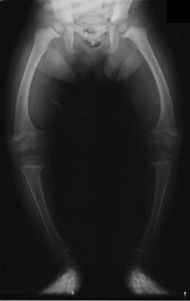

Рахит

В период разгара прогрессируют изменения костной системы: остеомаляция грудной клетки, нижних конечностей, избыточный остеогенез (рахитические «чётки», «браслетки», лобные и теменные бугры черепа). Ребёнок может отставать в физическом и психическом развитии.

Возникшие при рахите деформации скелета остаются и во взрослом возрасте: нарушение осанки, изменения грудной клетки, костей нижних конечностей. У женщин перенесённый в детстве рахит может быть причиной сужения малого таза, что может затруднить течение родов и потребовать проведение кесарева сечения.